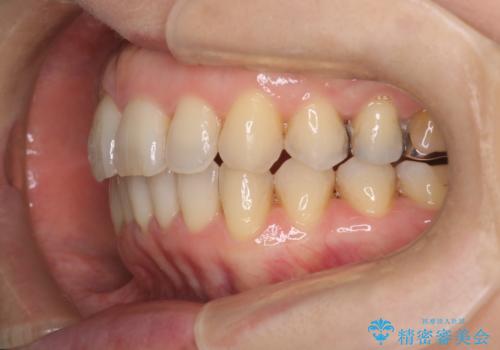

今回の治療では、右上5番の抜歯スペースを活用して八重歯(3番)を後方へ誘導しました。

インビザライン独自の3Dシミュレーションに基づき、必要な歯だけをピンポイントで動かすことで、抜歯を伴う大きな移動も効率的に行いました。

治療の結果、突出していた八重歯はきれいなアーチに収まり、左右対称でバランスの取れた口元になりました。インビザラインは自由に取り外しができるため、治療期間中も口腔内を清潔に保ちやすく、患者様もストレスなく治療を完了されました。